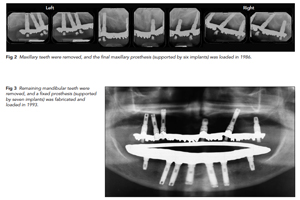

THIRTY-TWO–YEAR SUCCESS OF DENTAL IMPLANTS IN PERIODONTALLY COMPROMISED DENTITION

Thomas J. Balshi, DDS, PhD, FACP1, Glenn J. Wolfinger, DMD, FACP2, Stephen F. Balshi, MBE3, Myron Nevins, DDS4, David M. Kim, DDS, DMSc5: Osseointegrated dental implants have become an integral factor in the replacement of missing teeth.